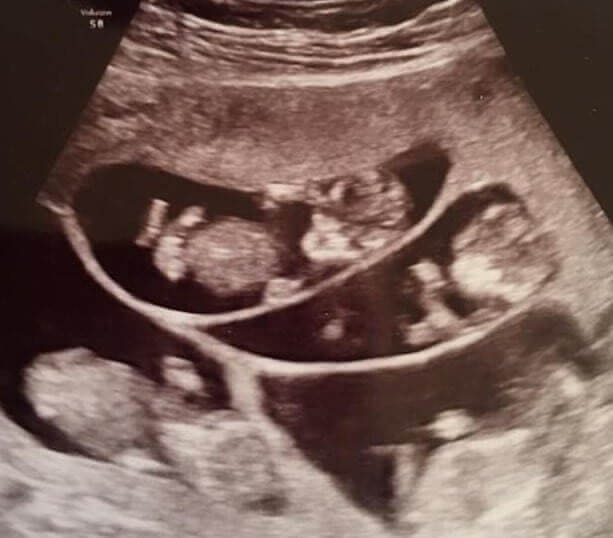

As the due date inched closer, each passing week was filled with tension and excitement. Carrying seven babies meant that premature labor was a constant concern.